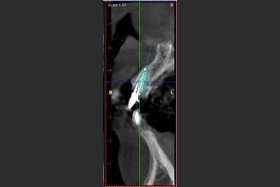

病患植牙前,拍攝3D立體斷層掃描。

當日立即模擬出最適宜的植牙位置。